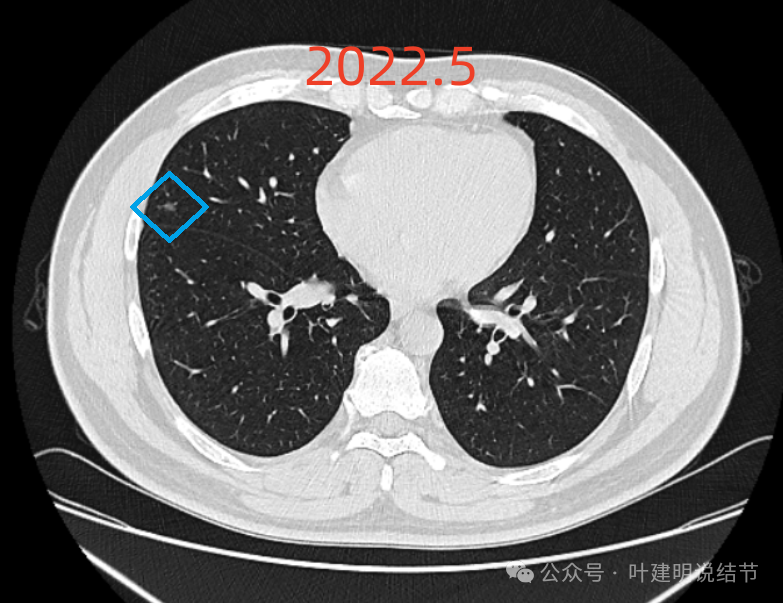

提供的影像资料是从2022年5月始的:

右中叶磨玻璃结节,密度较右下的略高,但仍说不上实性或混合密度,轮廓较清,缺乏膨胀性,邻近胸膜没有牵拉。